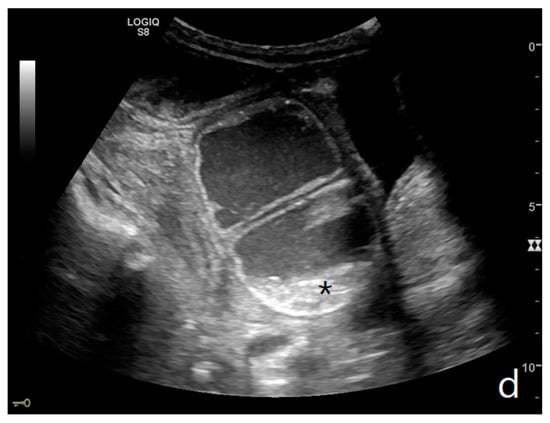

Figure 4.

A complicated SBO in a 69-year-old male with gastric cancer and peritoneal carcinosis. Ultrasound images show long (a) and axial (b) evaluations of a fluid-filled, dilated small bowel loop with hyperechogenic floating material (shown with an asterisk) (b,d). Bowel peristalsis was absent. Mild parietal and valvulae conniventes thickening are present (c,d). Downstream loops present normal caliber (bowel jump diameter). Free fluid is interposed between bowel loops (black arrow) (b).